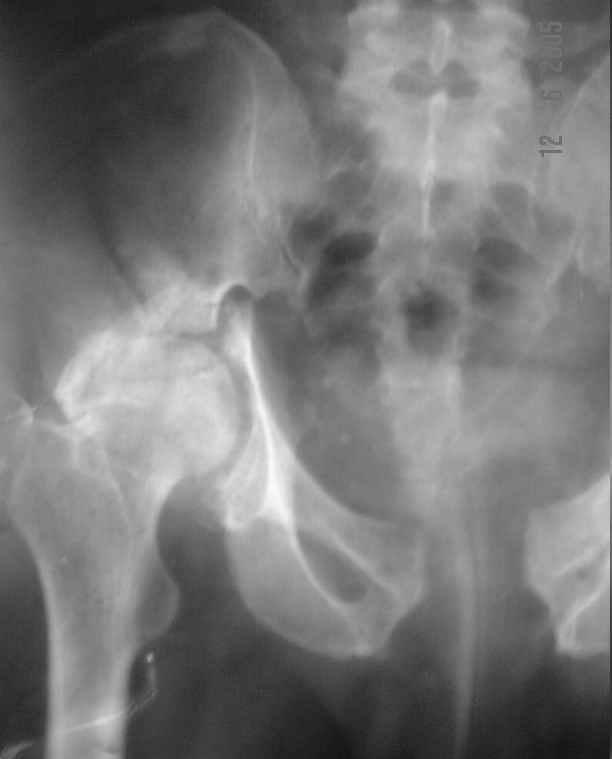

He gives history of being on skin traction for 3,5months. After that he was advised partial weight bearing to be graduated to full weight bearing. Now the patient has difficulty in weight bearing as it is painful. He can walk a few steps only with the help of a walker. Hip movements are restricted and painful. Fl-90* ER-10* IR-0, shortening-4cm. He also had # of humerus and radius/ulna, which were plated and have united. The serial x-rays of the pelvis/Hip during these 5 months show that the hip joint has been in the same position. I have the CT pictures also but not digitalized as yet.

It is a displaced and ununited fracture of the acetabulum, probably type C (AO). The pelvis is not fractured from what one can see of the sacro iliac joint.

Our experience showes, that reposition and stabilization pelvis in zone of old acetabular fractures with bone grafting are very traumatic and not effective due head AVN and hip arthrosis.